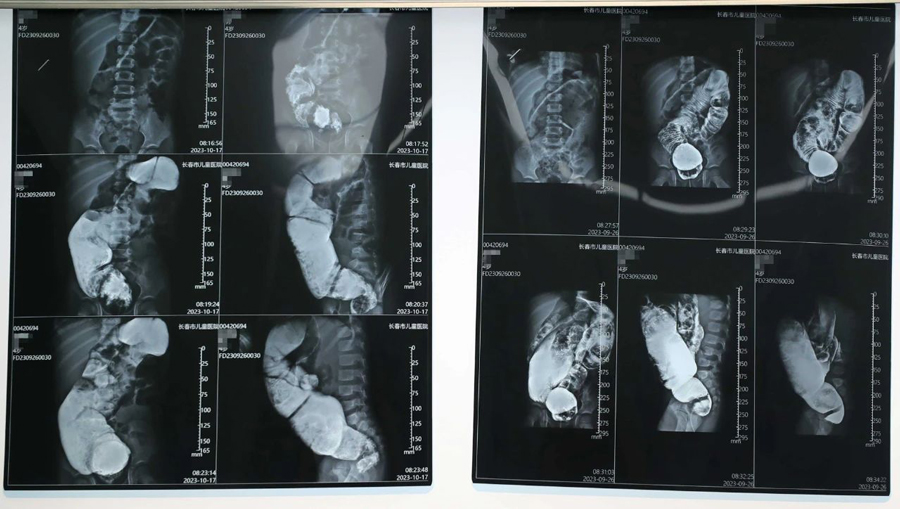

小旭本应在出生后3—6个月手术最佳,但因种种原因,治疗被拖延了。检查中医生发现,小旭为短段型巨结肠,因病程太长,导致肠管梗阻扩张严重、病情复杂,其中,扩张肠管最宽处可达12cm。手术切除缺乏神经节细胞的狭窄肠段及扩张失去正常功能的扩张段肠管,这是目前最有效的治疗方法。医生经过与家长反复沟通,确定了手术治疗方案。

经过充分的术前准备,小旭的肠道具备了手术条件,在完成相关检查和化验后,10月21日,首都医科大学附属北京儿童医院移植科主任、普通外科副主任、医学博士张廷冲,携手啪啪网 普外、新生儿外科主任崔钊团队,以及麻醉科、手术室人员,共同组成手术团队,行腹腔镜辅助下巨结肠根治术。张廷冲博士主刀,团队默契配合,先游离盆腔病变肠管,这一操作要求精细、精确解剖,难度很大,一旦损伤输尿管、盆神经和盆底肌肉,容易日后出现大小便失禁。术中取快速病理,使手术切除病变肠管更为精准、可靠。接下来,打开肛门黏膜层,拖出切除肠管,将保留的正常肠管与肛管黏膜吻合。在团队的共同努力下,手术的一系列操作都非常顺利,切除病变肠管约45cm,实现了精准、微创、安全、美观。